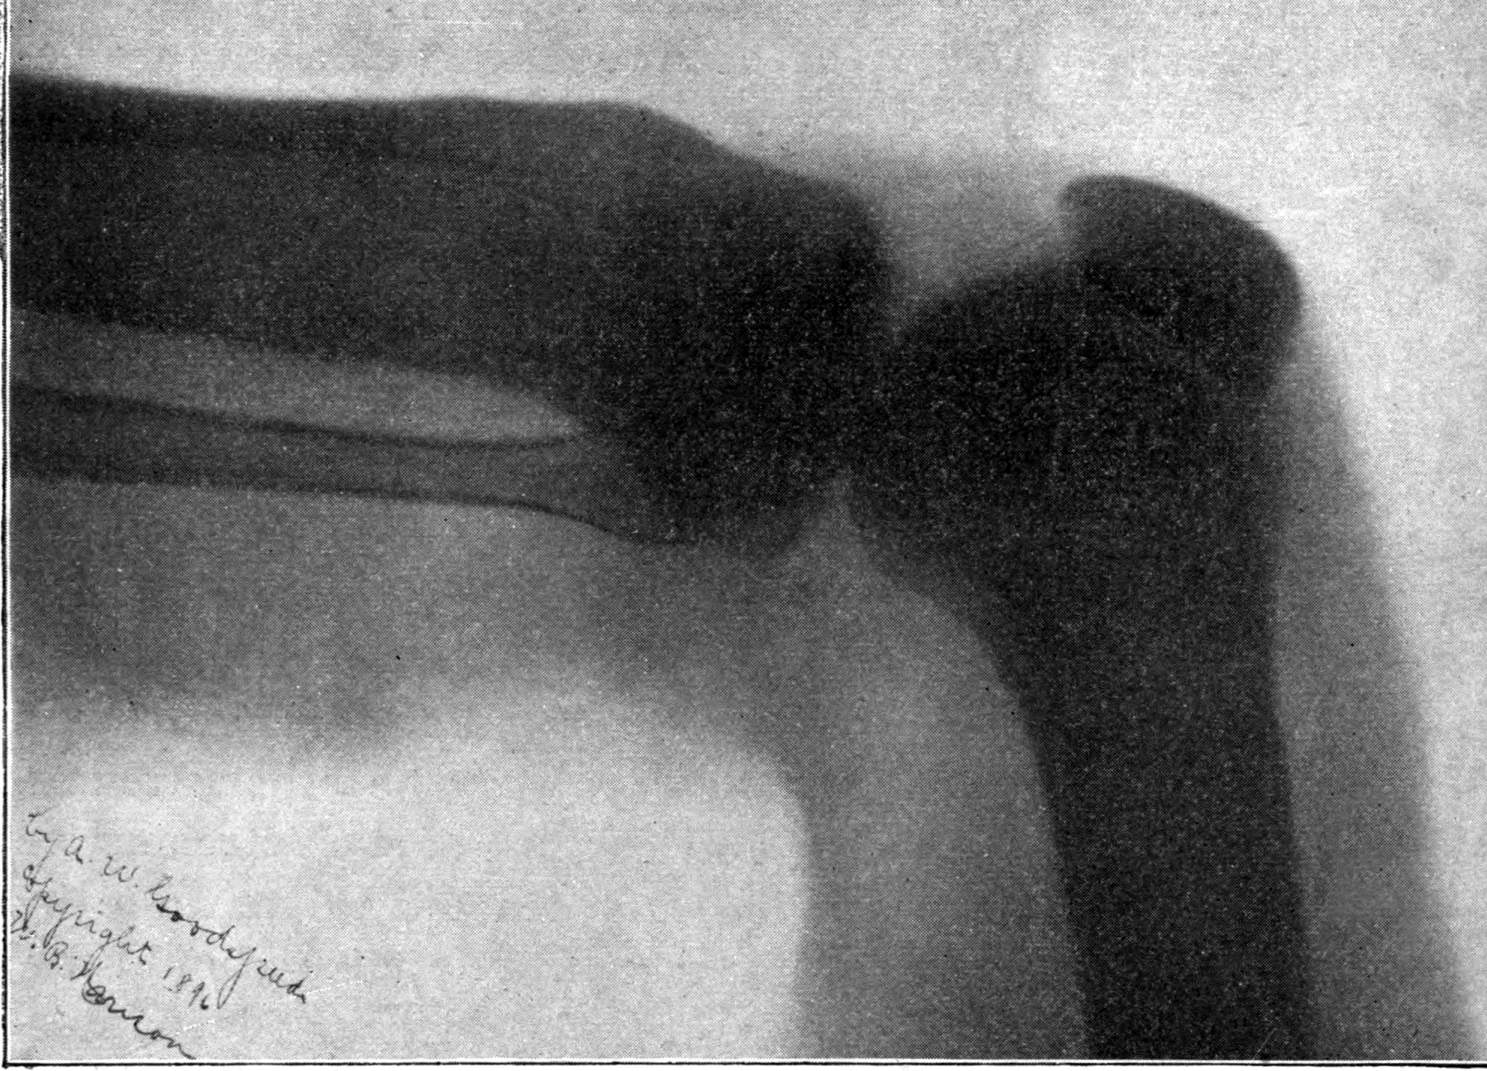

Fig. 2.—Broken Arm, Overlapping.

(Due to defective setting.)

FROM SCIAGRAPHS BY PROF. DAYTON C. MILLER. § 204.

117. Transposition of Phosphorescent Spot and of Cathode Rays without a Magnet. Salvioni, Elster, Geitel, and Tesla